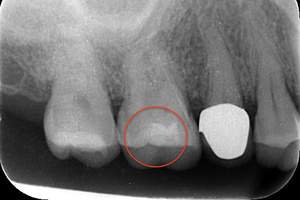

C3の虫歯治療方法

写真のレントゲンを見て頂くとわかると思います。赤丸の歯は、黒い影が歯の真ん中の黒い部分に達していますね。これが虫歯が歯の神経に達しているレントゲン写真になります。このような場合は、虫歯を取り除き歯の神経の治療が必要になり、その後に土台やかぶせ物の治療をします。

レントゲンは、柔らかければ柔らかいほど黒く写り、硬ければ硬い程白く写ります。そのため、虫歯は黒く写ってきます。

虫歯症例のレントゲン写真。虫歯は黒く写ります。